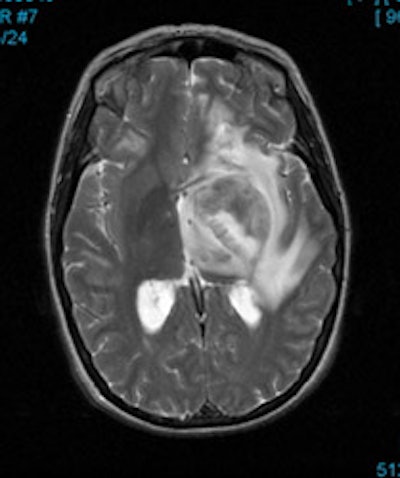

CNS malignancy: MR and thallium scan images from a patient with an enlarging brain lesion. On the MR image, note how edema makes detection of the primary tumor difficult. The thallium scan (right) demonstrates a focal area of tracer accumulation highly suspicious for CNS malignancy. A sterotactic biopsy was performed and the lesion was found to be a CNS lymphoma. |